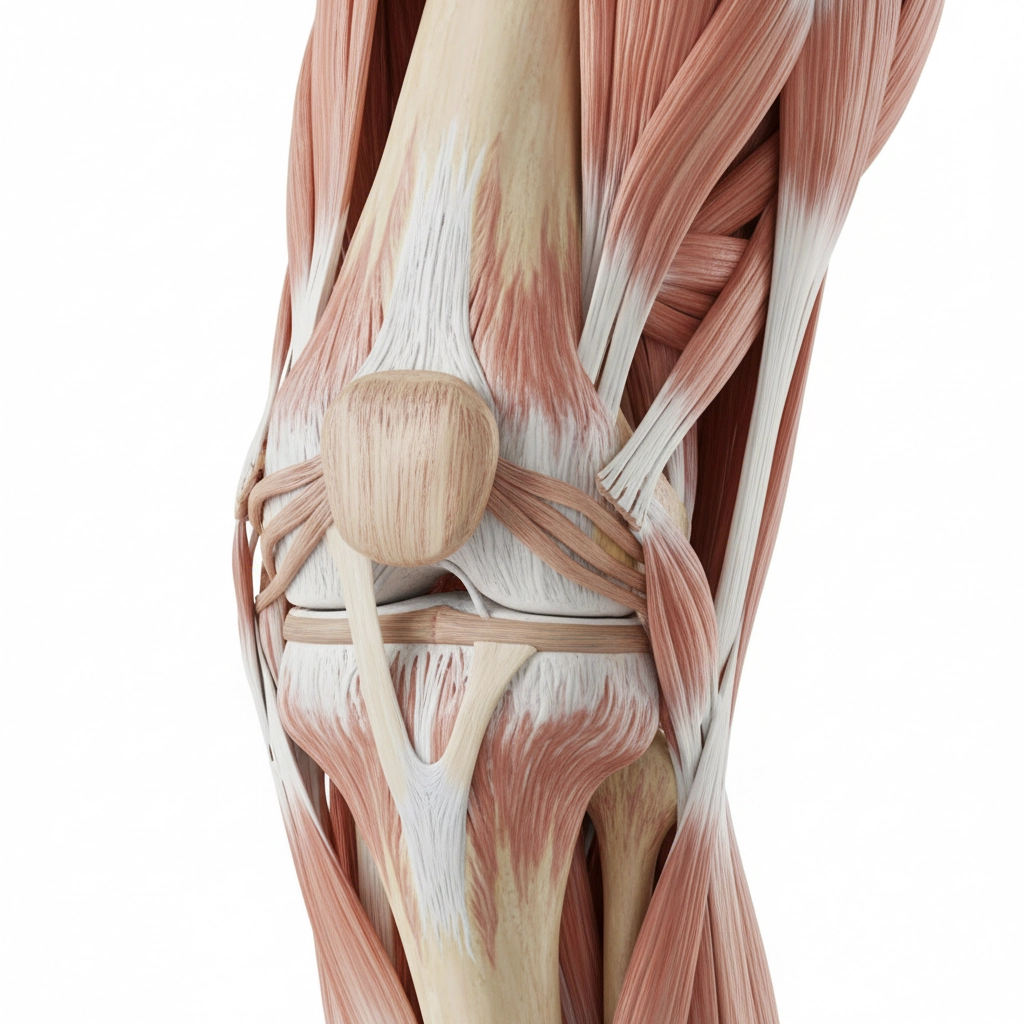

Joint Inflammation Treatment

CLAYER's anti-inflammatory properties work faster and safer than imported alternatives, with no risk of heavy metal accumulation in your joints over time.